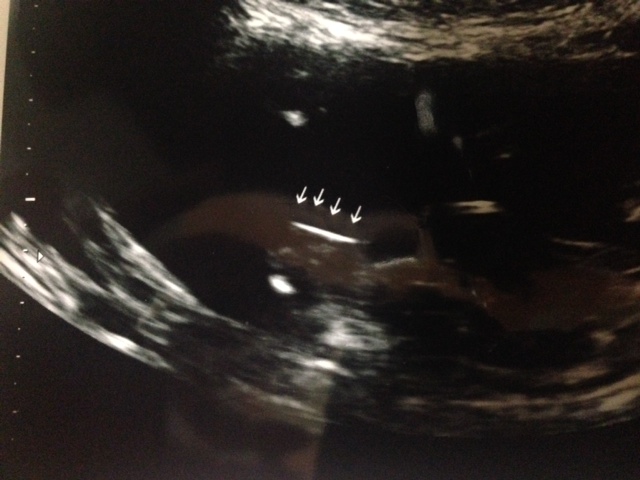

PS - Here's a second pic the tech said connoted gender. She said that flat line said girl - but she didn't say what it actually was.

Attachment 14592